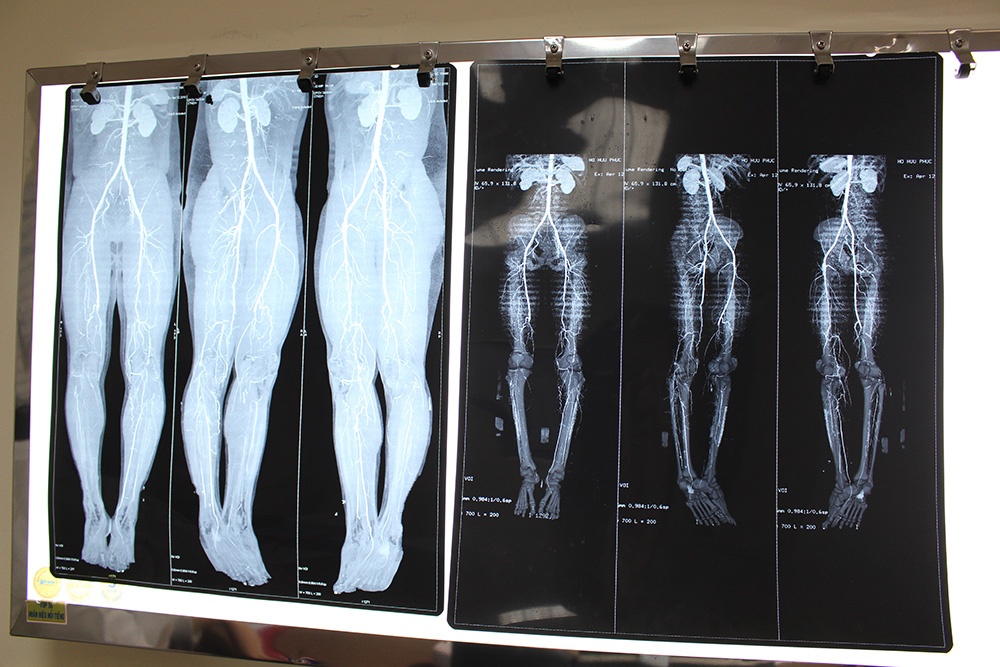

| Kỹ thuật chụp mạch máu kỹ thuật số xóa nền DSA đã phát hiện chàng trai bị tắc mạch máu chân phải, kịp thời giữ lại chi trước khi hoại tử. Ảnh: Phú Mỹ |

Tại đây, qua kiểm tra và chụp CT mạch máu chân phải, bác sĩ phát hiện bệnh nhân bị tắc hoàn toàn nhiều động mạch. Sau khi hội chẩn, bác sĩ quyết định dùng phương pháp can thiệp nội mạch với kỹ thuật chụp mạch máu kỹ thuật số xóa nền DSA nhằm xác định chính xác các thương tổn, bệnh lý mạch máu trước khi chỉ định can thiệp mạch. Kết quả chụp DSA cho thấy bệnh nhân đã bị tắc hoàn toàn các động mạch đùi nông, động mạch khoeo, động mạch chày trước và động mạch chày sau.